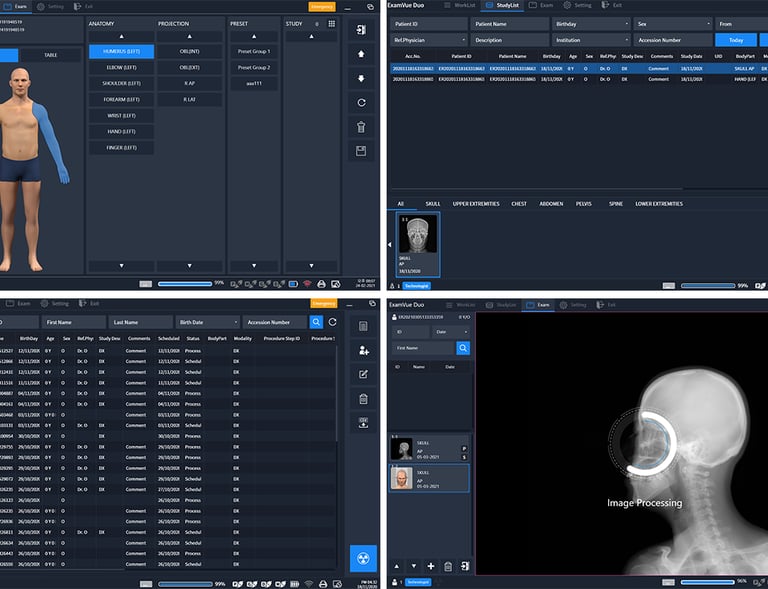

PACS DE EXAMVUE

EXAMVUE DUO ACQUISITION SOFTWARE

Diseñado para optimizar la captura de imágenes radiográficas con la más alta calidad y eficiencia

Acceso Seguro y Rápido a tus Imágenes Médicas

En LinkMedic llevamos la radiología al siguiente nivel con nuestro sistema PACS en la nube. Procesa, comparte y almacena radiografías digitales de forma eficiente y sin límites geográficos. Garantizamos acceso seguro, imágenes de alta calidad y una experiencia ágil que optimiza tu flujo de trabajo, mejorando la atención de tus pacientes en cualquier momento y lugar.